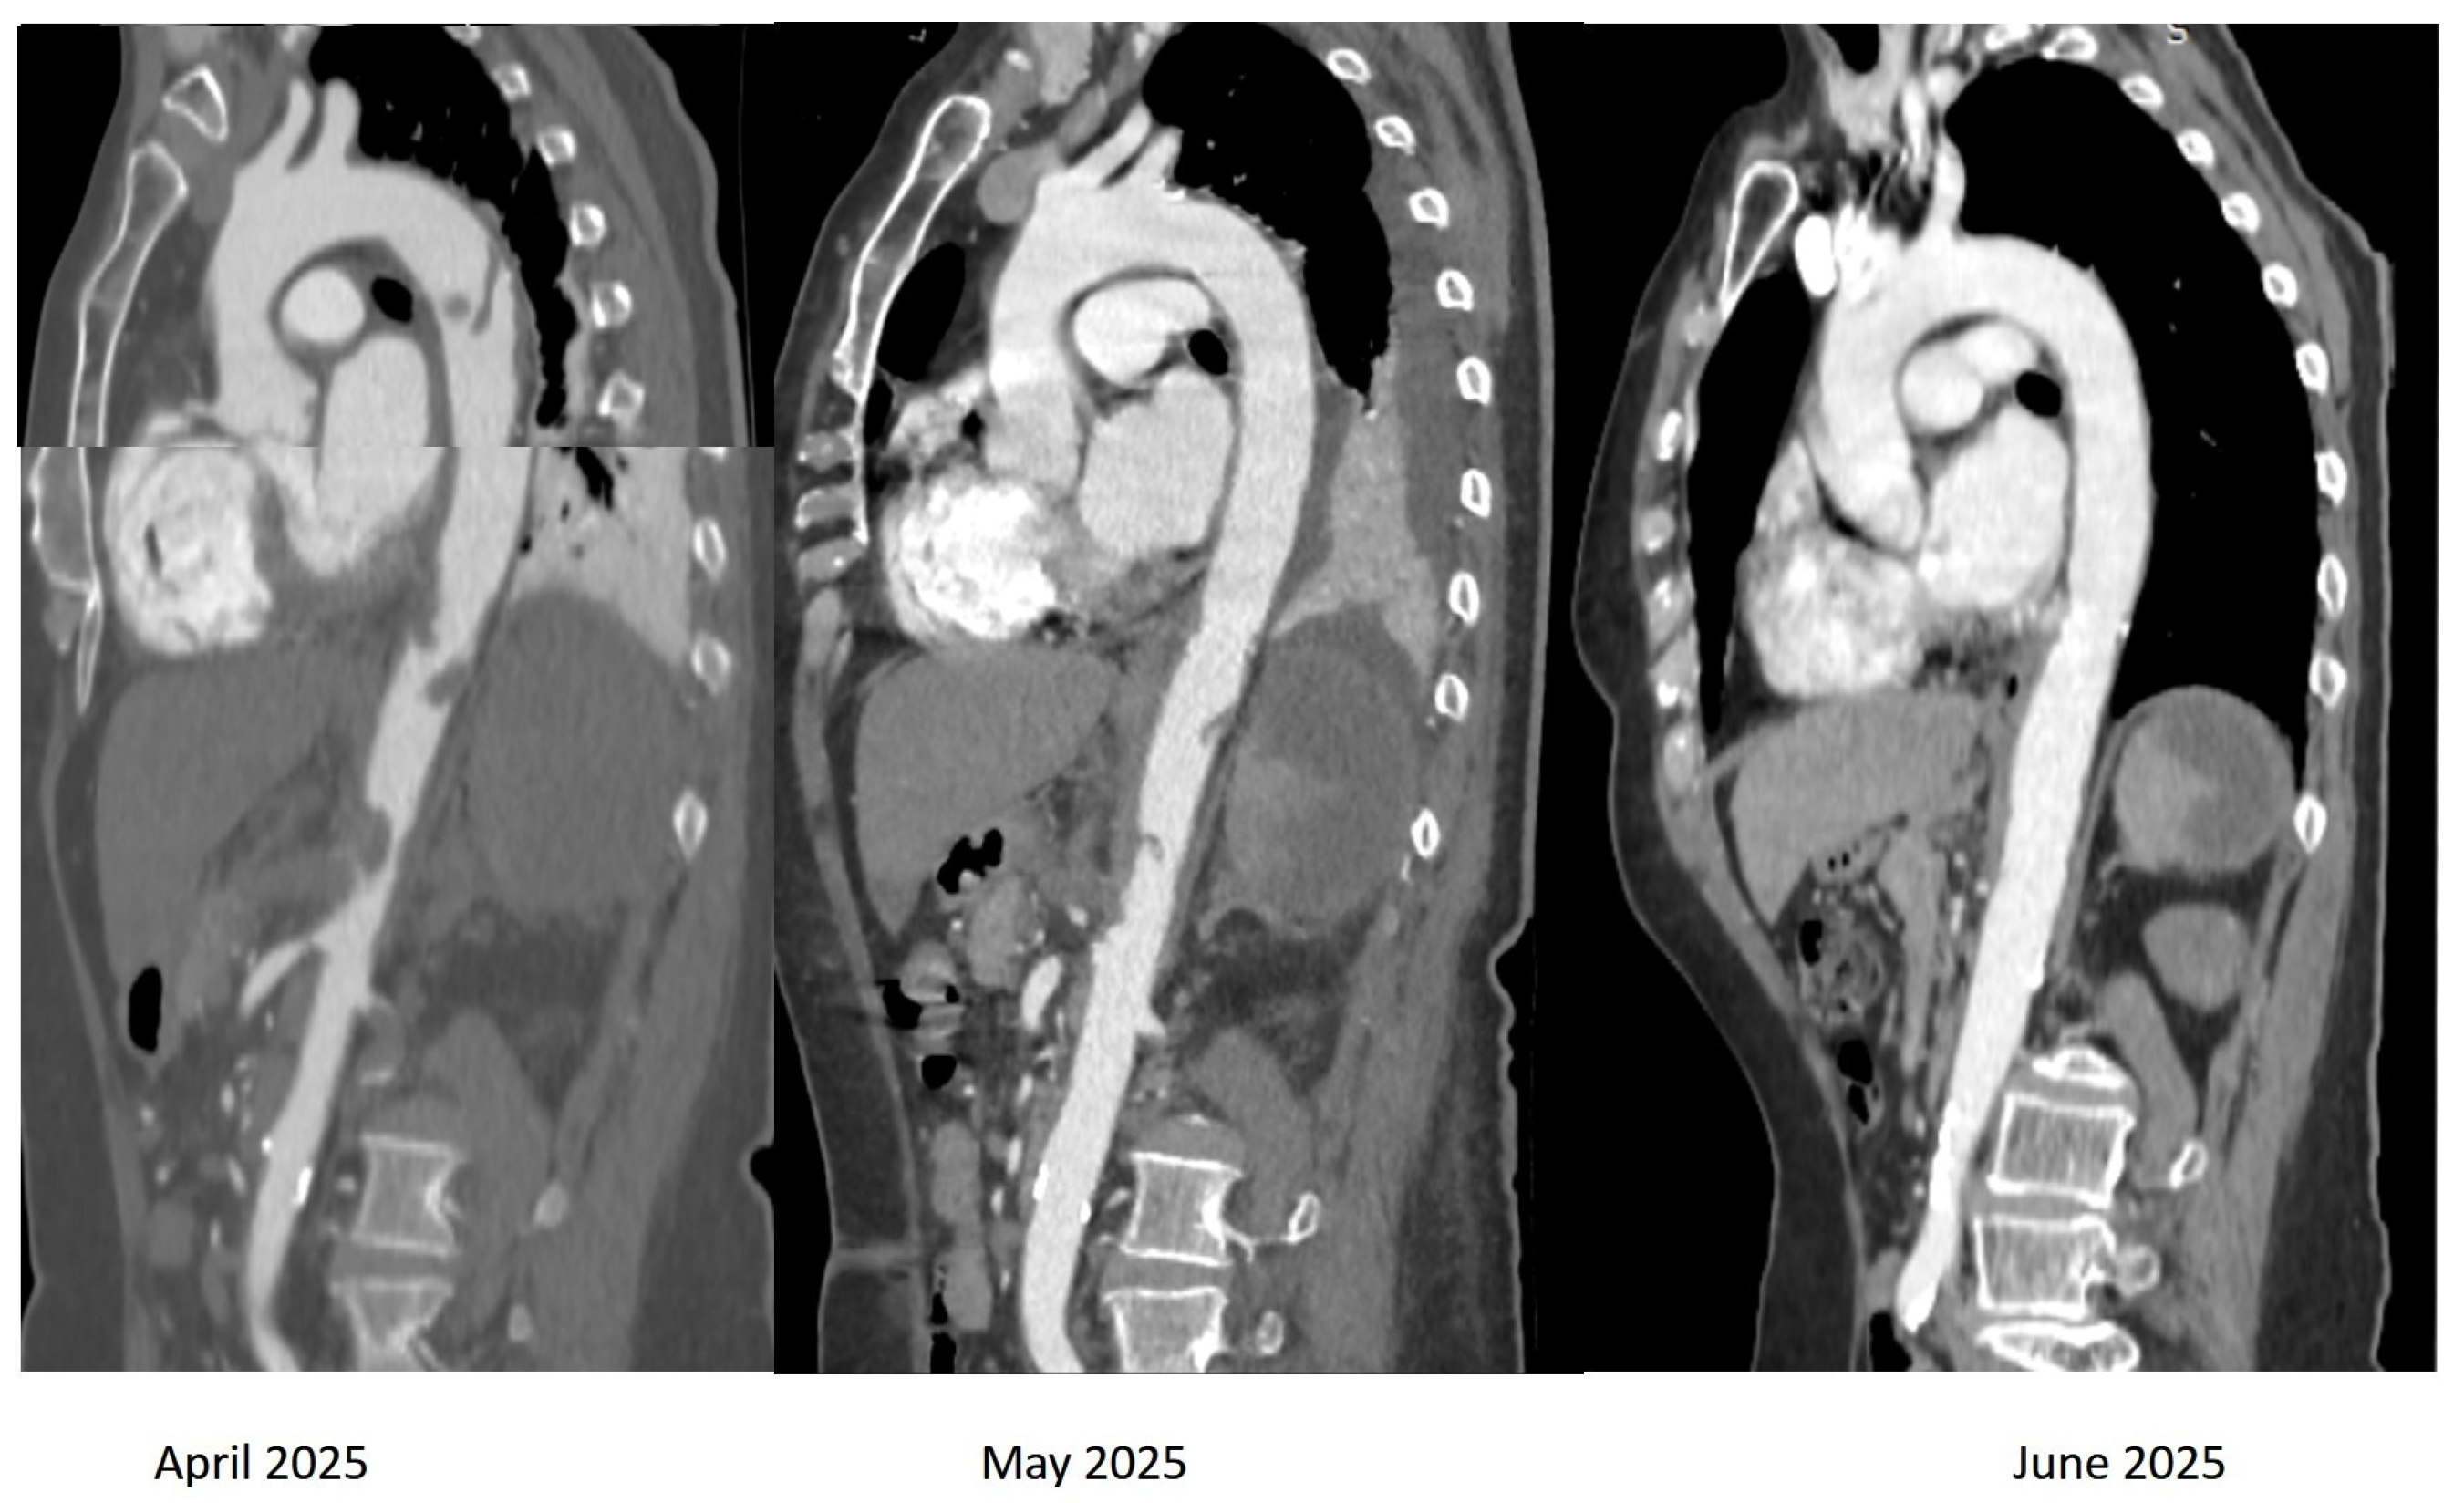

2. Case Presentation